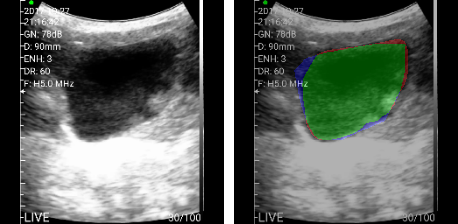

- Мобильный УЗИ с искусственным интеллектом – определяет контуры, размер, толщину стенки мочевого пузыря, объем, емкость, однородность его содержимого (рис. 9).

Рис. 9. УЗИ мочевого пузыря с ИИ.